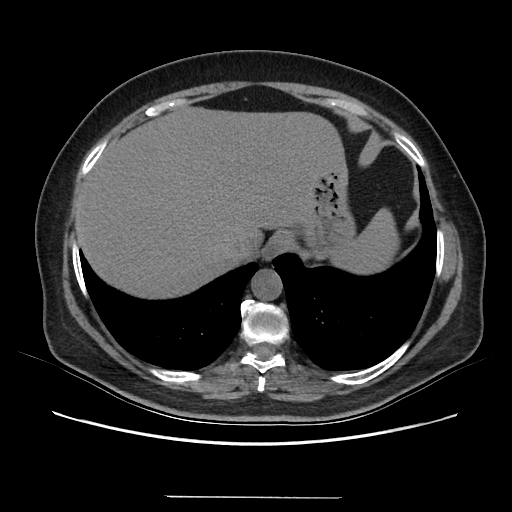

Image Grid

4Γ—3 grid: Rows show different image types (Original NATIVE, Reconstructed NATIVE, Original VENOUS, Generated VENOUS), Columns show windowing techniques (No Window, Lung Window, Mediastinum Window)

Generated VENOUS CT scan (A→B translation)

Full window (WL 1023.5, WW 4095 β†’ Low βˆ’1024, High +3071)